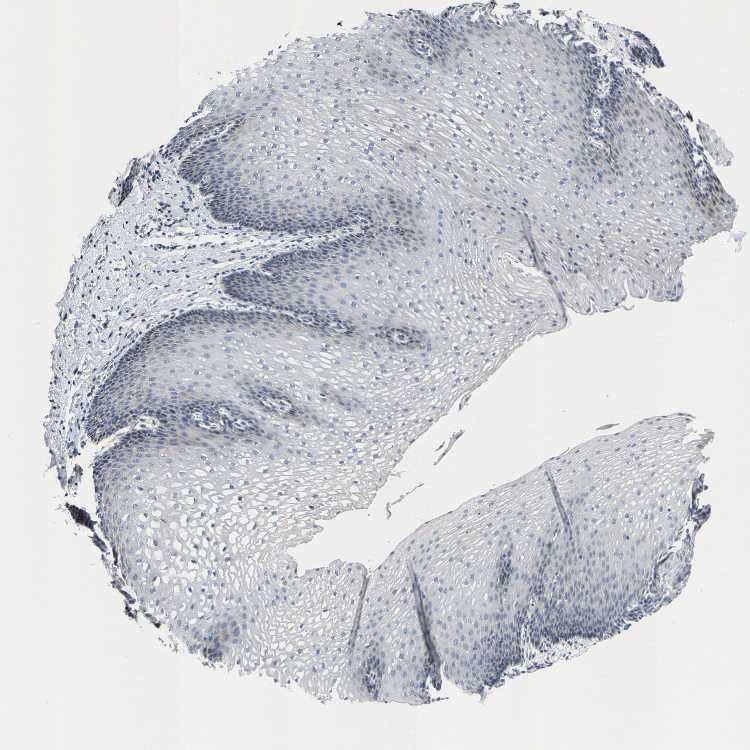

ESOPHAGUS - Antibody stainingi

Antibody staining in the annotated cell types in the current human tissue is reported as not detected, low, medium, or high, based on conventional immunohistochemistry profiling in selected tissues. This score is based on the combination of the staining intensity and fraction of stained cells.

Each image is clickable and will lead to virtual microscopy that enables deeper exploration of all samples and also displays staining intensity scores, fraction scores and subcellular localization as well as patient and tissue information for each sample.

Antibody HPA021196

Squamous epithelial cells Not detected